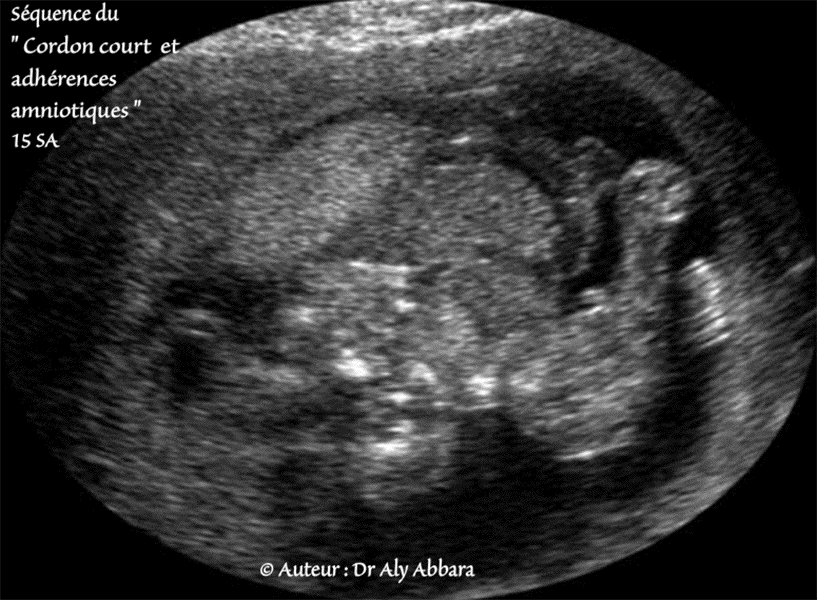

Séquence cordon ombilical court

Séquence du cordon ombilical court avec adhérences amniotiques

(Fœtus âgé de 15 SA).

• Série d'images échographiques montrant les anomalies anatomiques caractérisant cette séquence polymalformative, à savoir :

un cordon très court, une large célosomie adhérant, ainsi le reste du tronc, à la face fœtale du placenta, puis des adhérences amniotiques étendues entre le tronc fœtal et l'amnios du sac ovulaire.

Parmi les autres anomalies associées on observe la présence d'une scoliose importante, une exencéphalie avec une dysmorphie faciale majeure, des anomalies des extrémités supérieures par compression et enfin, des pieds bots.